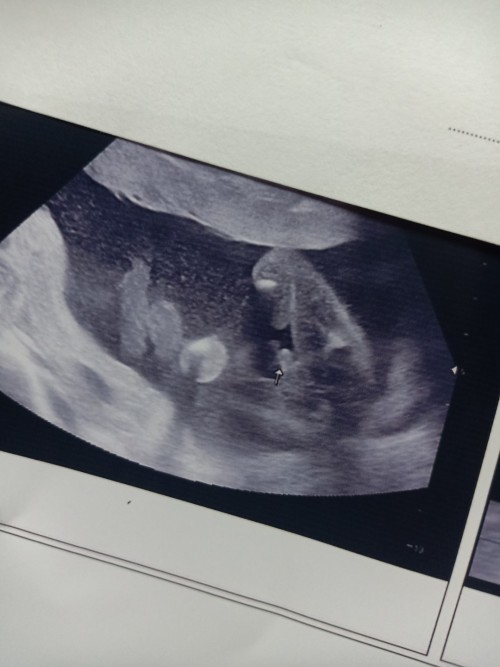

อยากทราบเพศของลูก

อยากรู้ว่าประมาณกี่สัปดาห์ถึงจะซาวด์เจอเพศลูกคะ#ขอบคุณสำหรับคำตอบค่ะ

บ้านนี้23 week เห็นเพศชัดมากเลยค่ะ

บ้านนี้ 19 w ค่าา ได้น้องผุ้ชาย..

ของเรา 13 วีคเห็นค่าาาาา

บ้านนี้เห็นตอน 17 w ค่ะ

บ้านนี้รู้ช่วง 20 วีค

เริ่ม16w ค่ะ